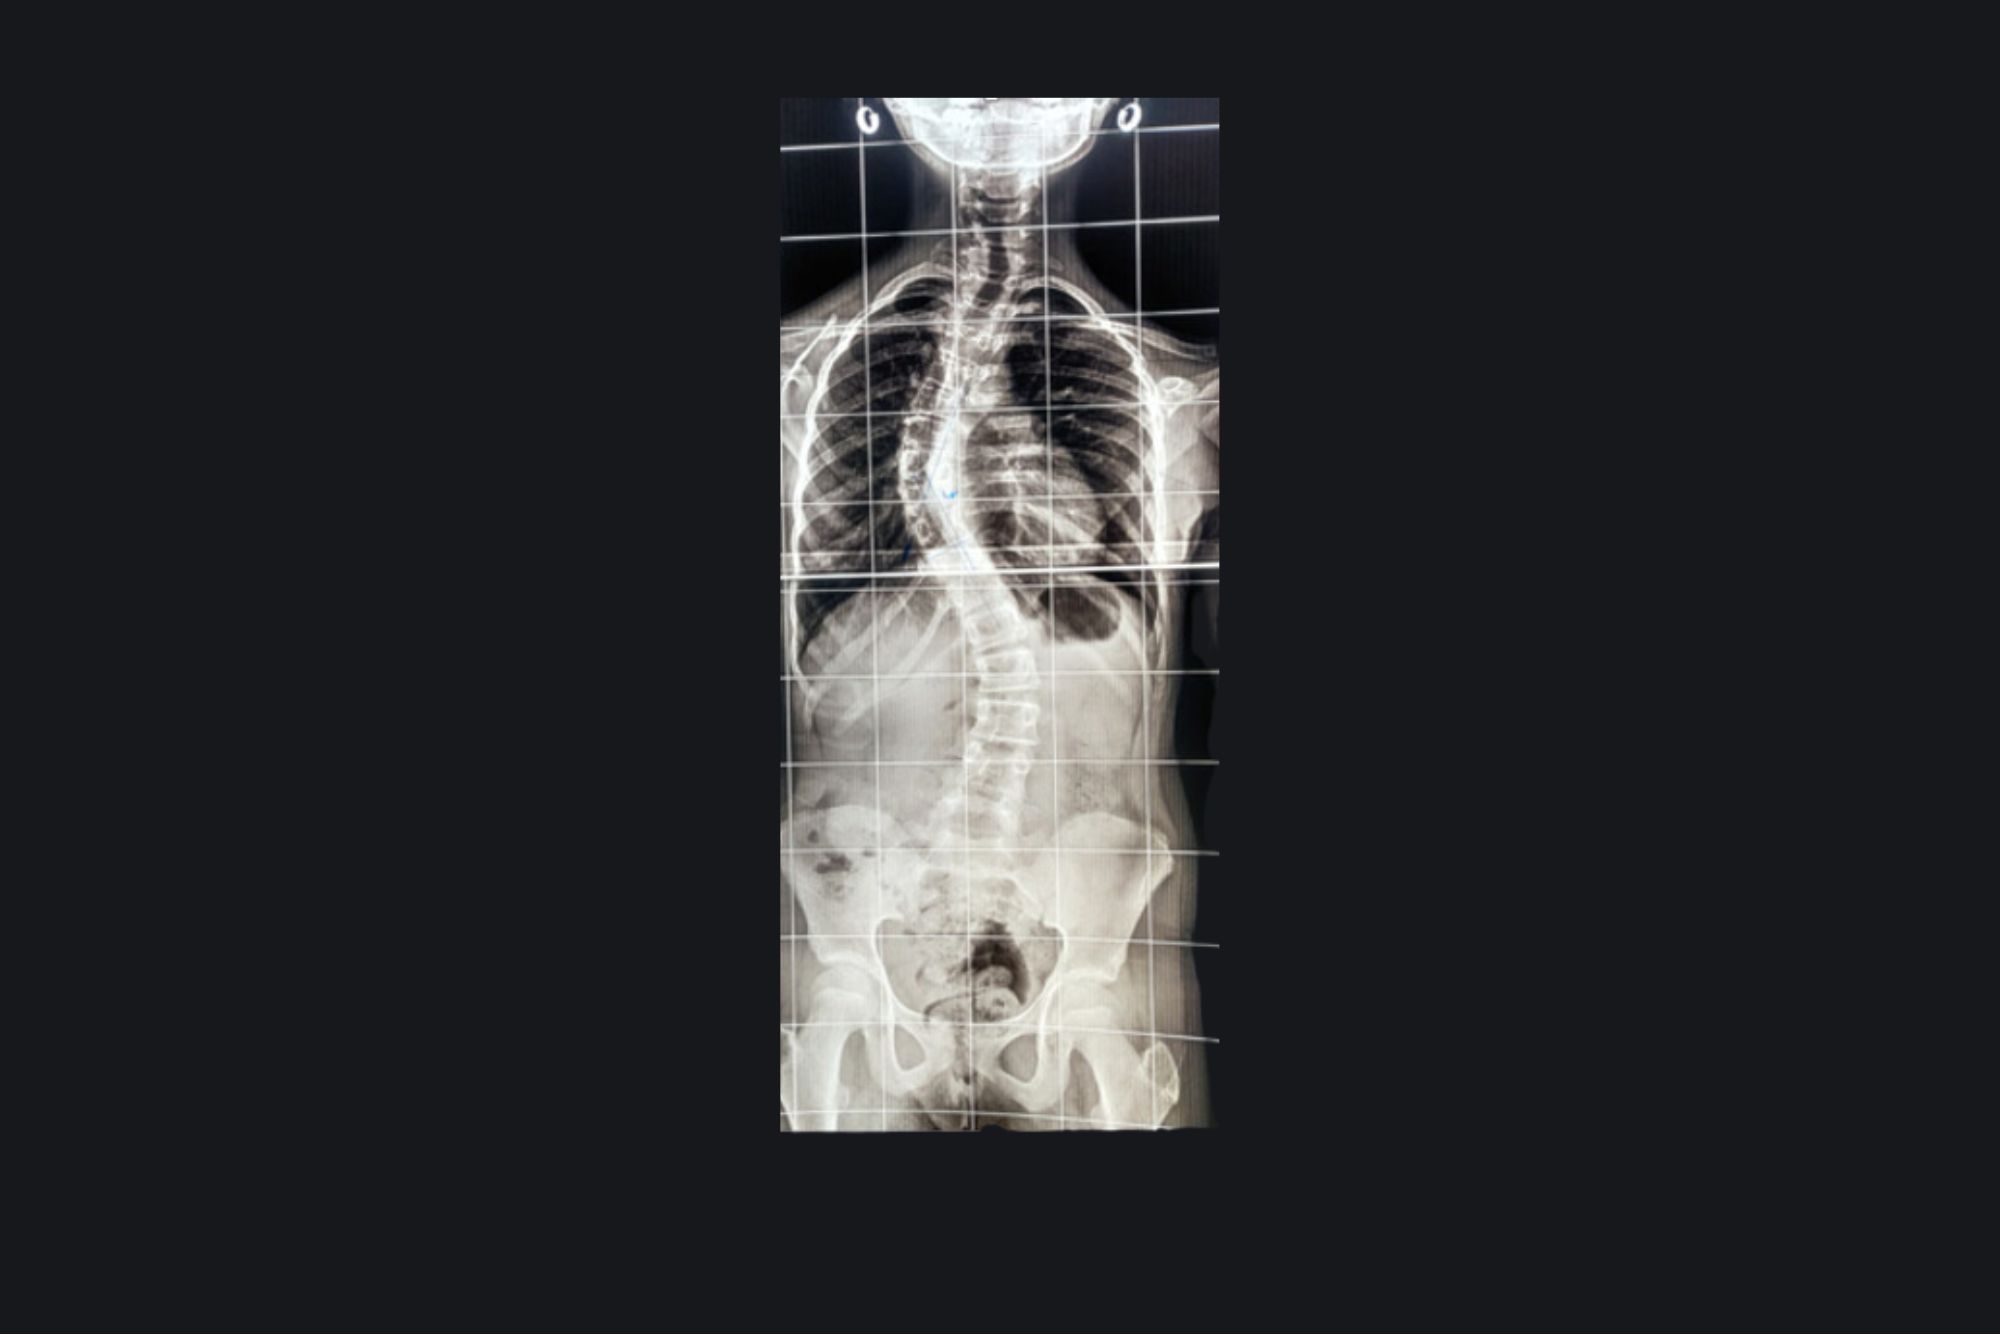

Deformity Of Back

Preoperative MRI

Postoperative MRI